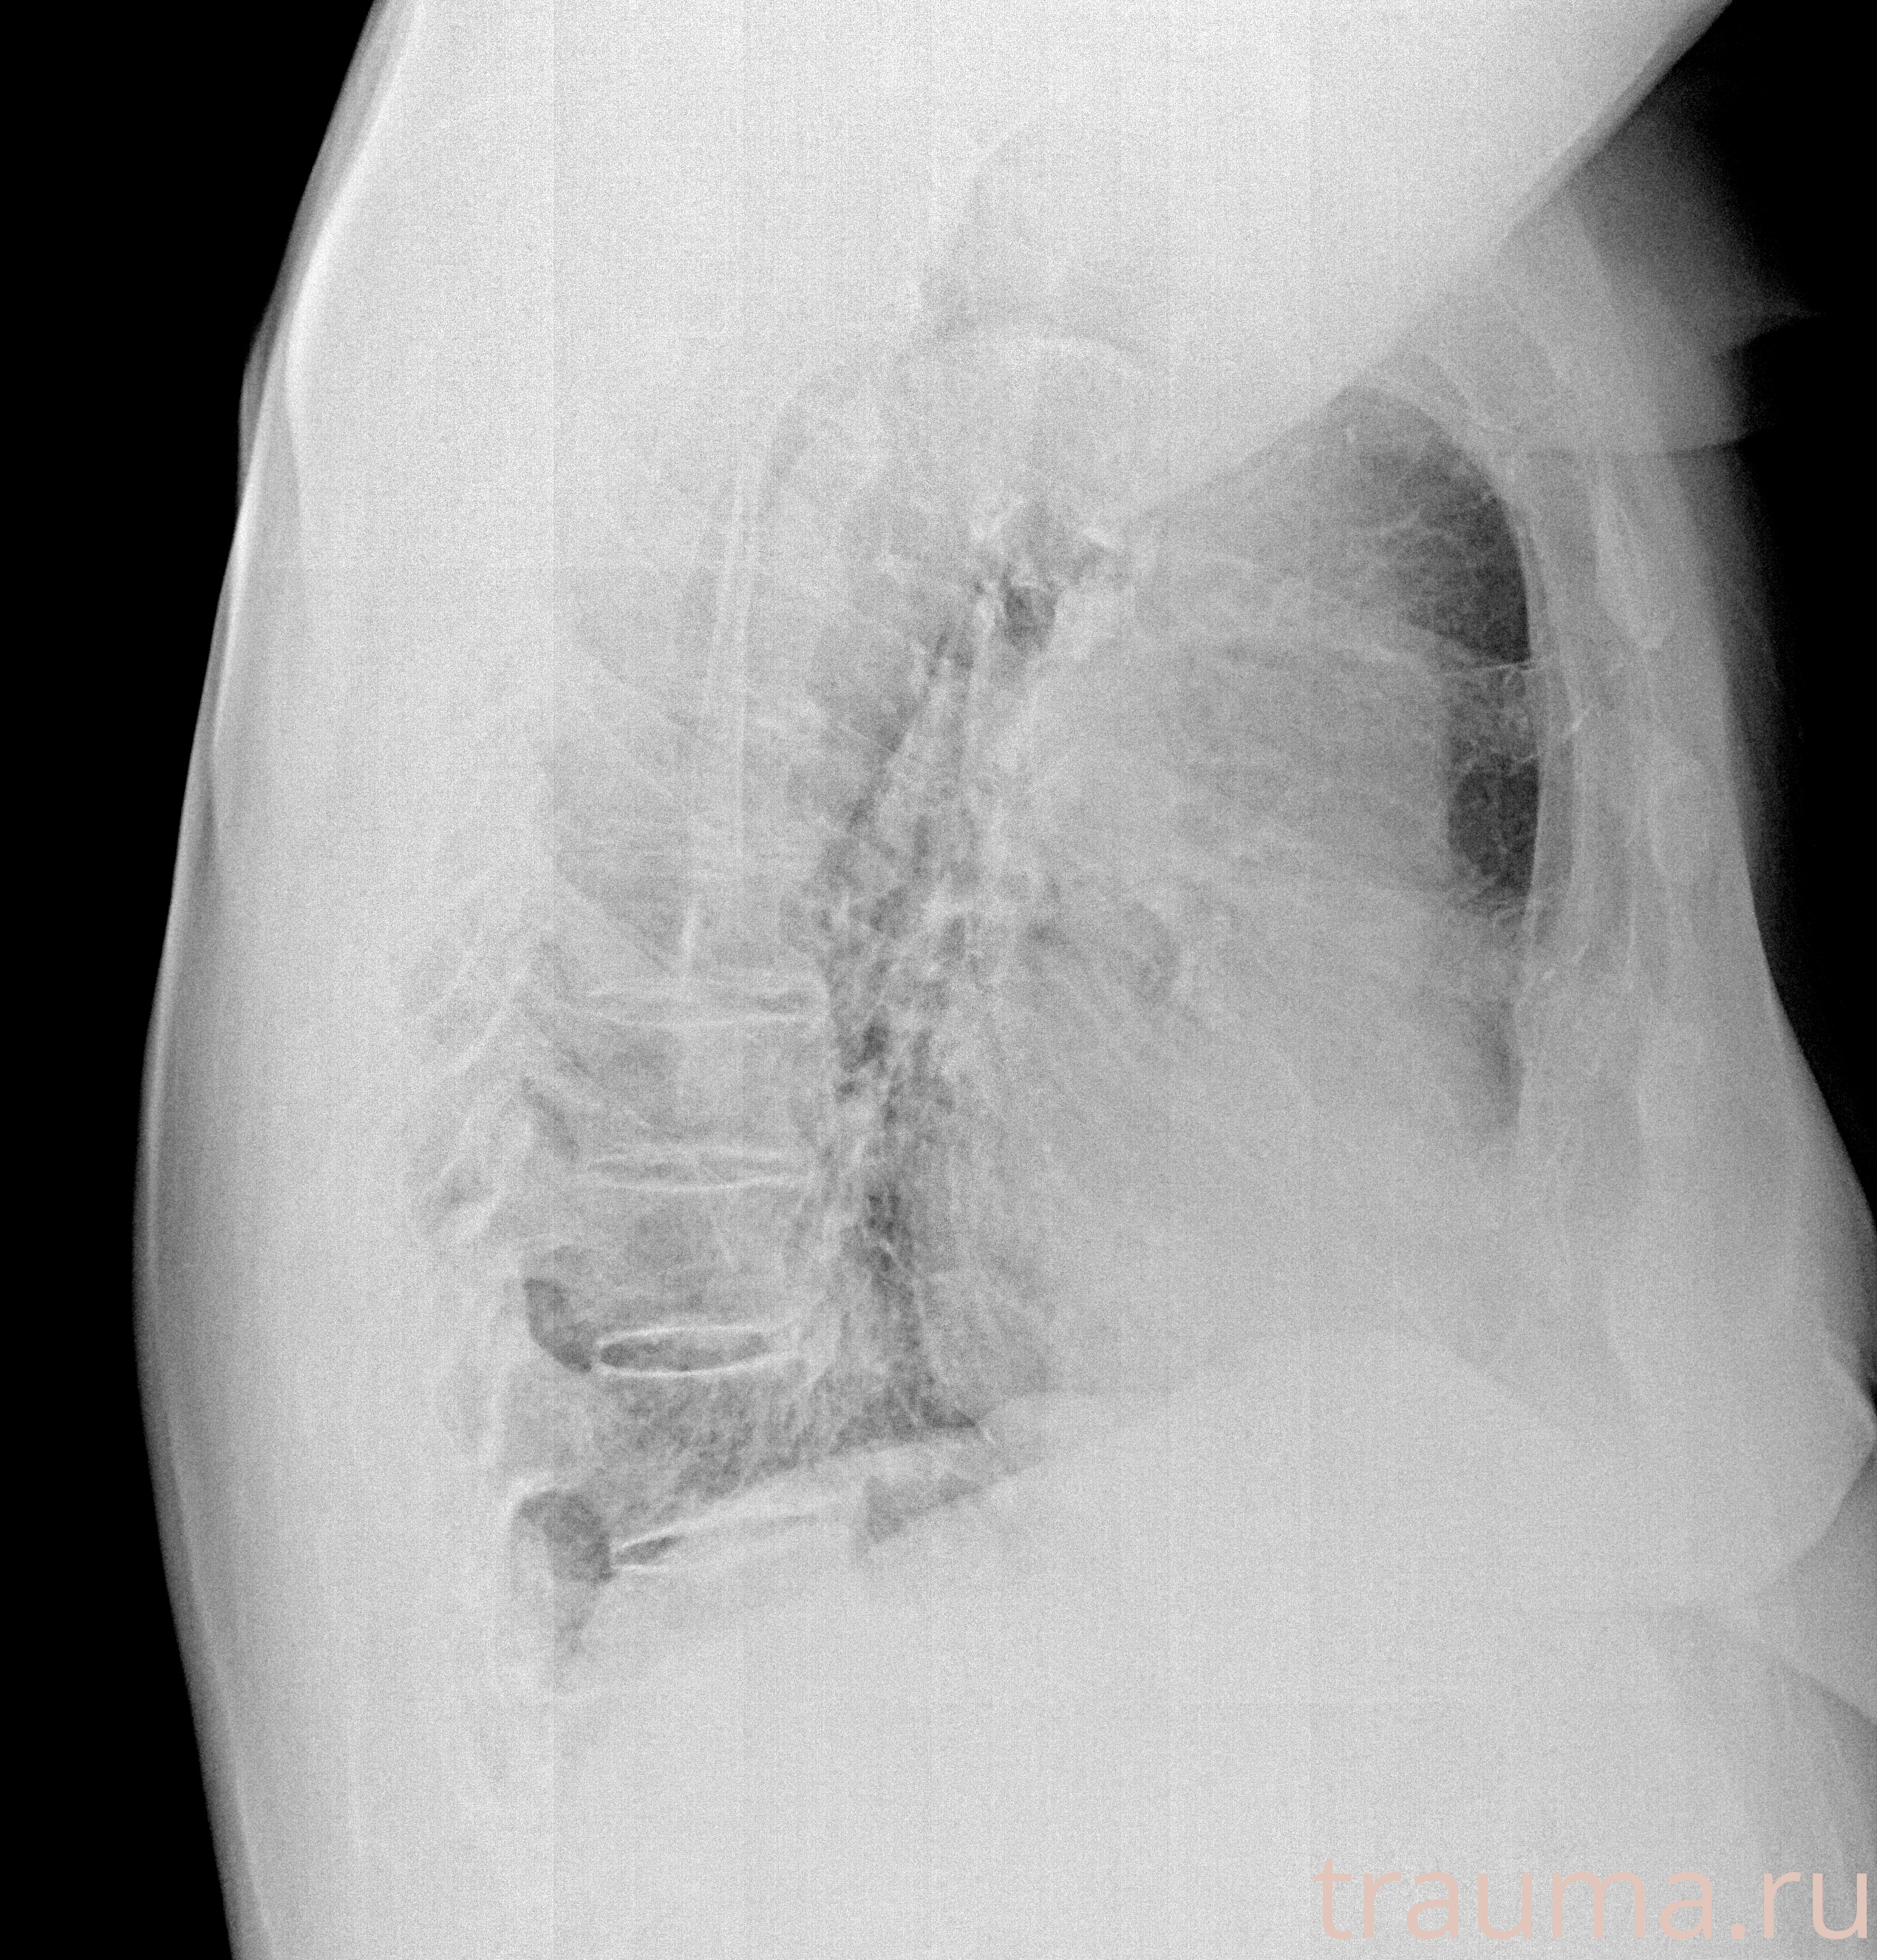

Рентгенограммы

Рентген на дому: по вашему адресу приезжает врач-рентгенолог, травматолог-ортопед с мобильным рентгеновским аппаратом, проводит диагностику травмы или заболевания, делает необходимые рентгенограммы, дает рекомендации по дальнейшему лечению. Получить качественные снимки в домашних условиях возможно благодаря уникальной методике, разработанной МосРентген Центром для института  Склифосовского

при переломе шейки бедра и пневмонии от компании МосРентген Центр - партнера Института имени Склифосовского